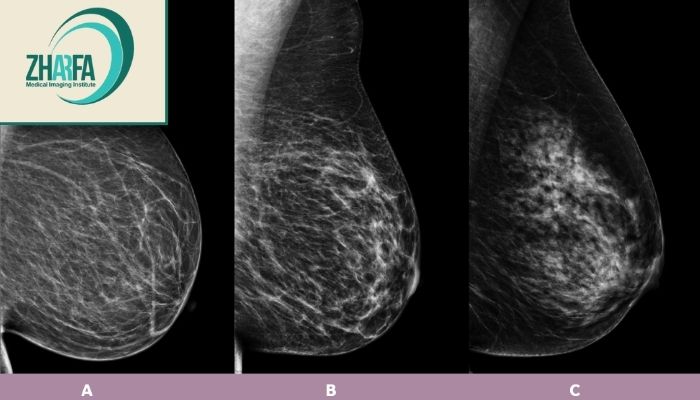

مقایسه ماموگرافی و سونوگرافی سینه